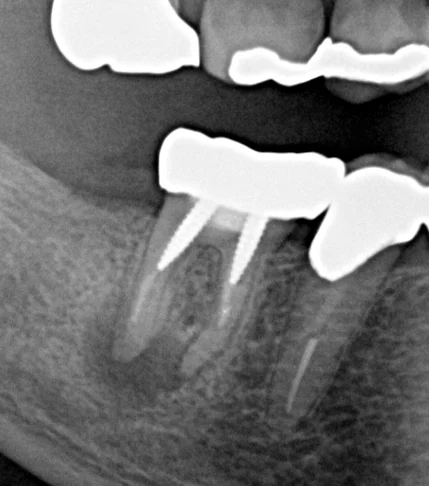

こちらが、初診時のレントゲン写真です。

このレントゲンだけ見ても、分かりづらいと思いますので、少し分かりやすく線を描いたものも載せます。